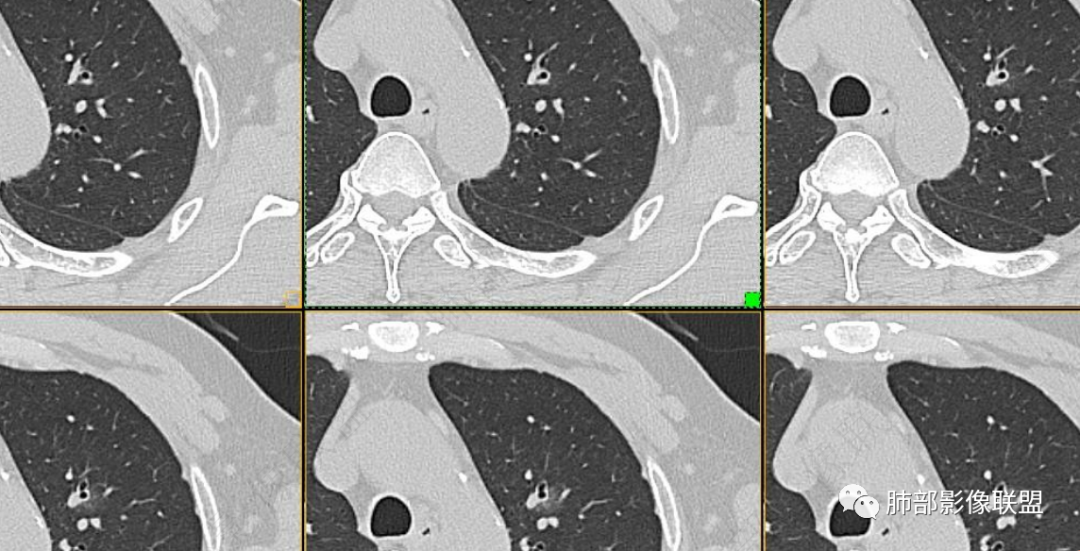

目前看支气管通畅

实性部分强化明显,边缘平直

2、病灶以实性密度为主,前、外侧蔓延,GGO部分边界清楚,部分欠清

支气管未见受明显侵犯,未见阻塞,壁增厚,狭窄或扩张。

软组织+重建;病灶实性部分不是类圆形,密度相对均匀柔和。

1、连续3年观察,病灶逐步增大,符合惰性恶性肿瘤。2、支气管壁增厚,腔内内壁无变化——病灶长轴沿支气管周围蔓延;朝外走,内侧没有,提示病灶间质为主,与支气管无关。